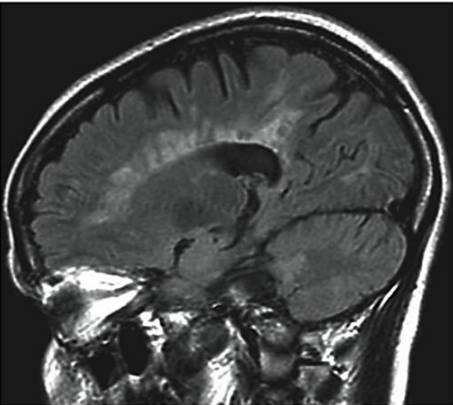

A imagem a seguir corresponde mais provavelmente a:

Uma das principais características dos craniofaringiomas é:

A imagem a seguir está relacionada a: